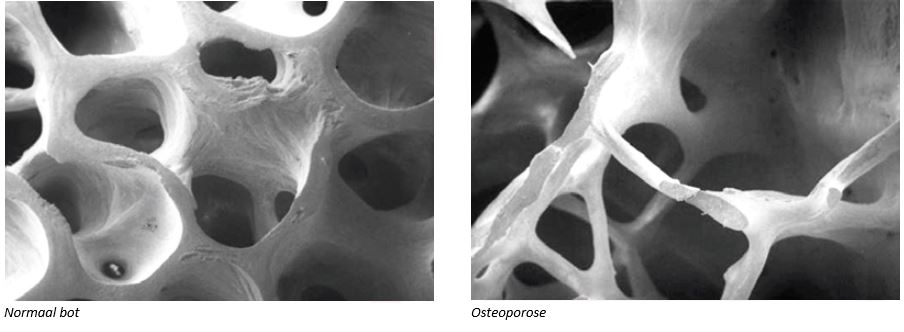

Wordt er meer botweefsel afgebroken dan aangemaakt? Dan wordt de botdichtheid minder; de natuurlijke gaatjes in het bot worden groter. De botten zijn dan minder sterk. We noemen dit osteoporose, in de volksmond ook wel botontkalking genoemd. Ernstige osteoporose kan botbreuken tot gevolg hebben, bijvoorbeeld van de pols, de heup of een ruggenwervel (ook wel wervelinzakking genoemd).